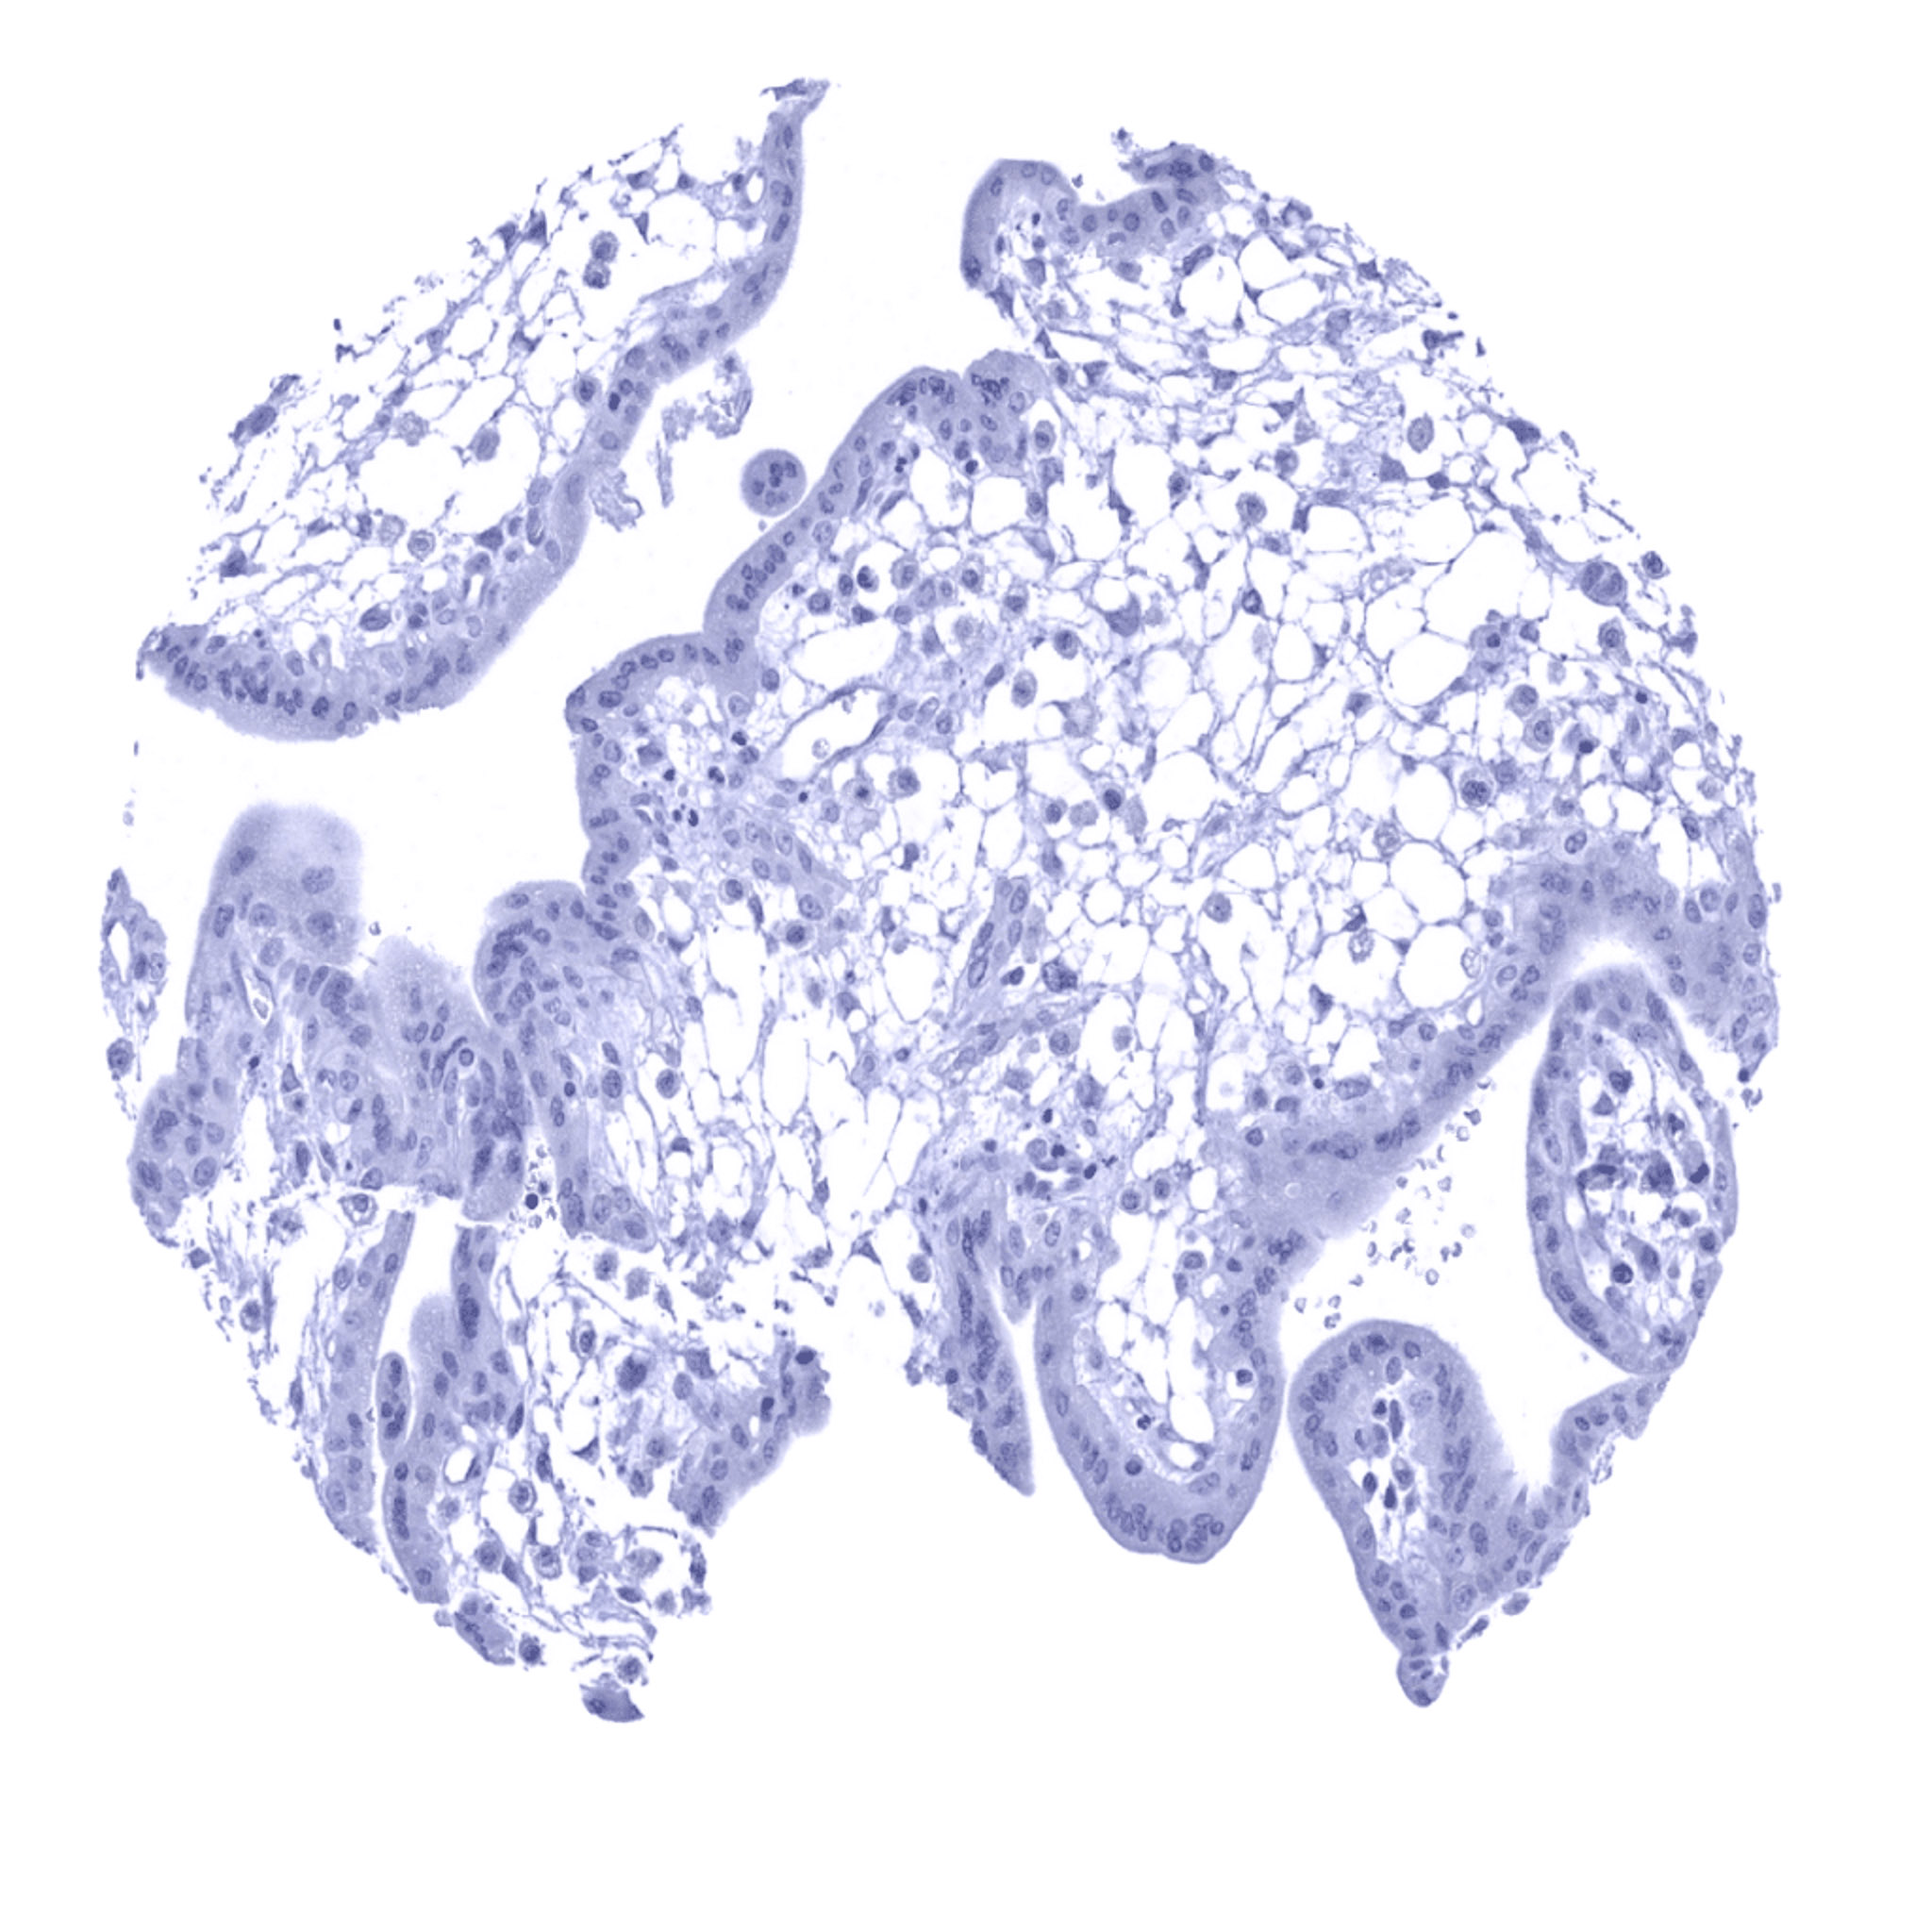

Placenta, early – A weak to moderate UPK1B immunostaining can be found in a fraction of syncytiotrophoblast cells of the placenta.

Placenta, early

Placenta, mature